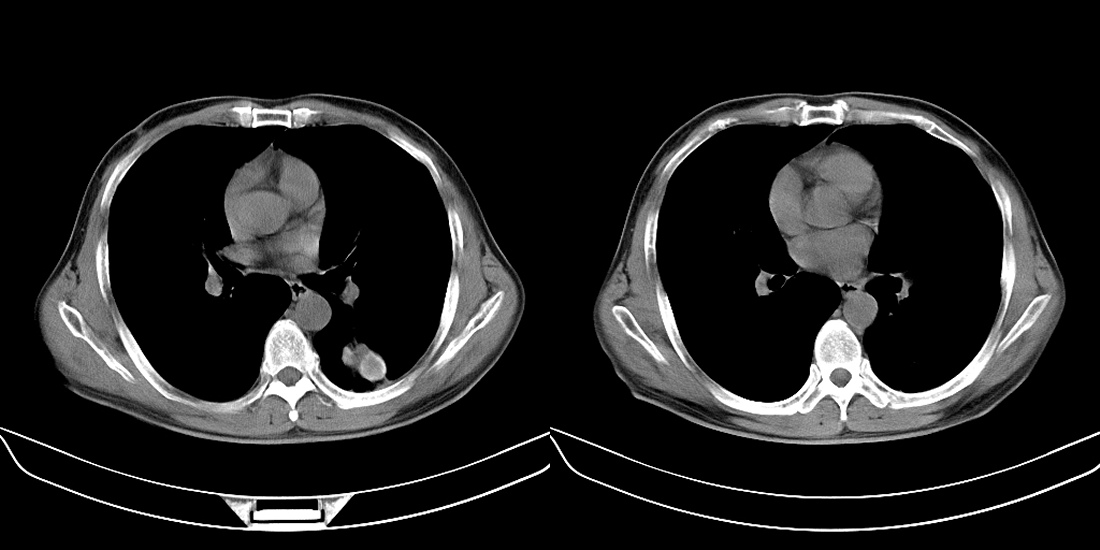

标题: CT10251:男性56岁,结核球? [打印本页]

标题: CT10251:男性56岁,结核球?

56岁男性,低热、消瘦,曾x线诊断肺结核。

两肺结核,左肺结核球。

双肺结核伴左上肺结核球形成